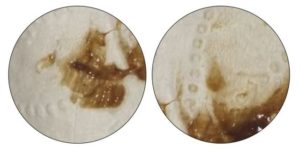

Обуславливается это тем, что во время сдачи анализа осуществляется соскабливание верхнего слоя слизистых оболочек, в результате чего они повреждаются и начинают кровить.

Кровь выделяется в небольших количествах, быстро окисляется под действием кислорода и приобретает темный оттенок. Поэтому наличие коричневых скудных выделений считается нормальным.